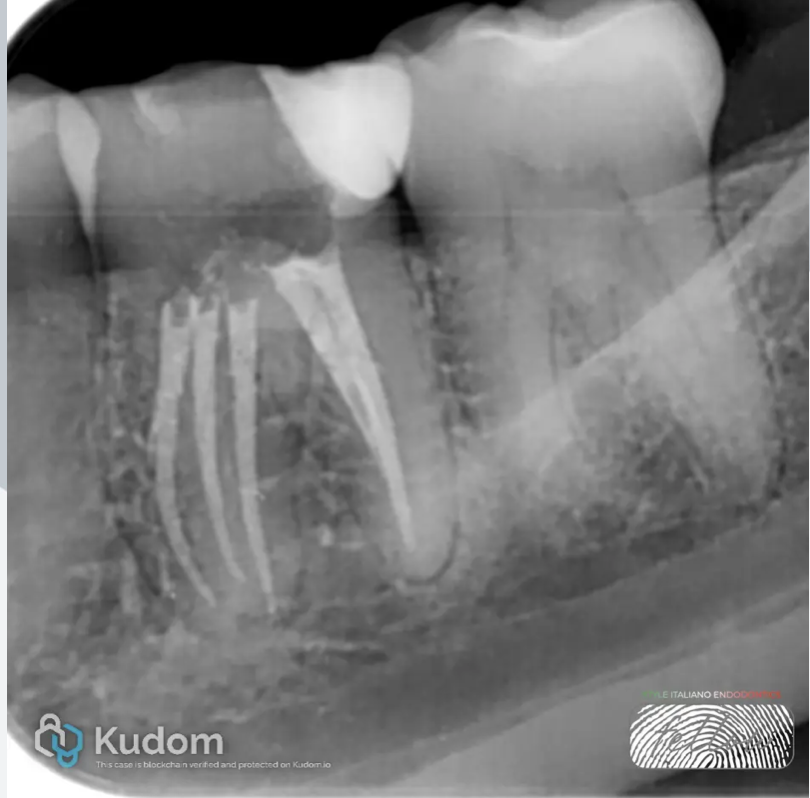

Fig. 2

Axial CBCT Slice:The analysis of the axial slice revealed the presence of a third, un-obturated canal in the mesial root of tooth 3.6, consistent with the Middle Mesial Canal